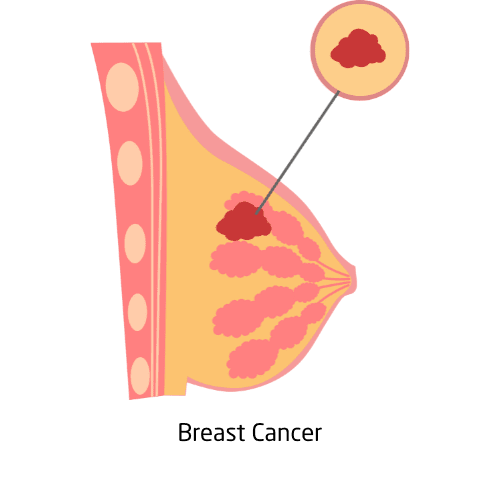

Breast cancer occurs when cells in the breast grow and divide uncontrollably, forming a tumor. It’s the most common cancer among women worldwide and can also affect men. Risk factors include age, genetics (such as BRCA mutations), lifestyle, and reproductive history. Early detection through mammograms, clinical exams, and self-checks greatly improves treatment success. Common symptoms include lumps, nipple discharge, or skin changes.

Treatment varies by stage and type, often involving surgery, chemotherapy, radiation, hormone therapy, or targeted drugs. Emotional support, survivor networks, and access to reliable information play a critical role in recovery.